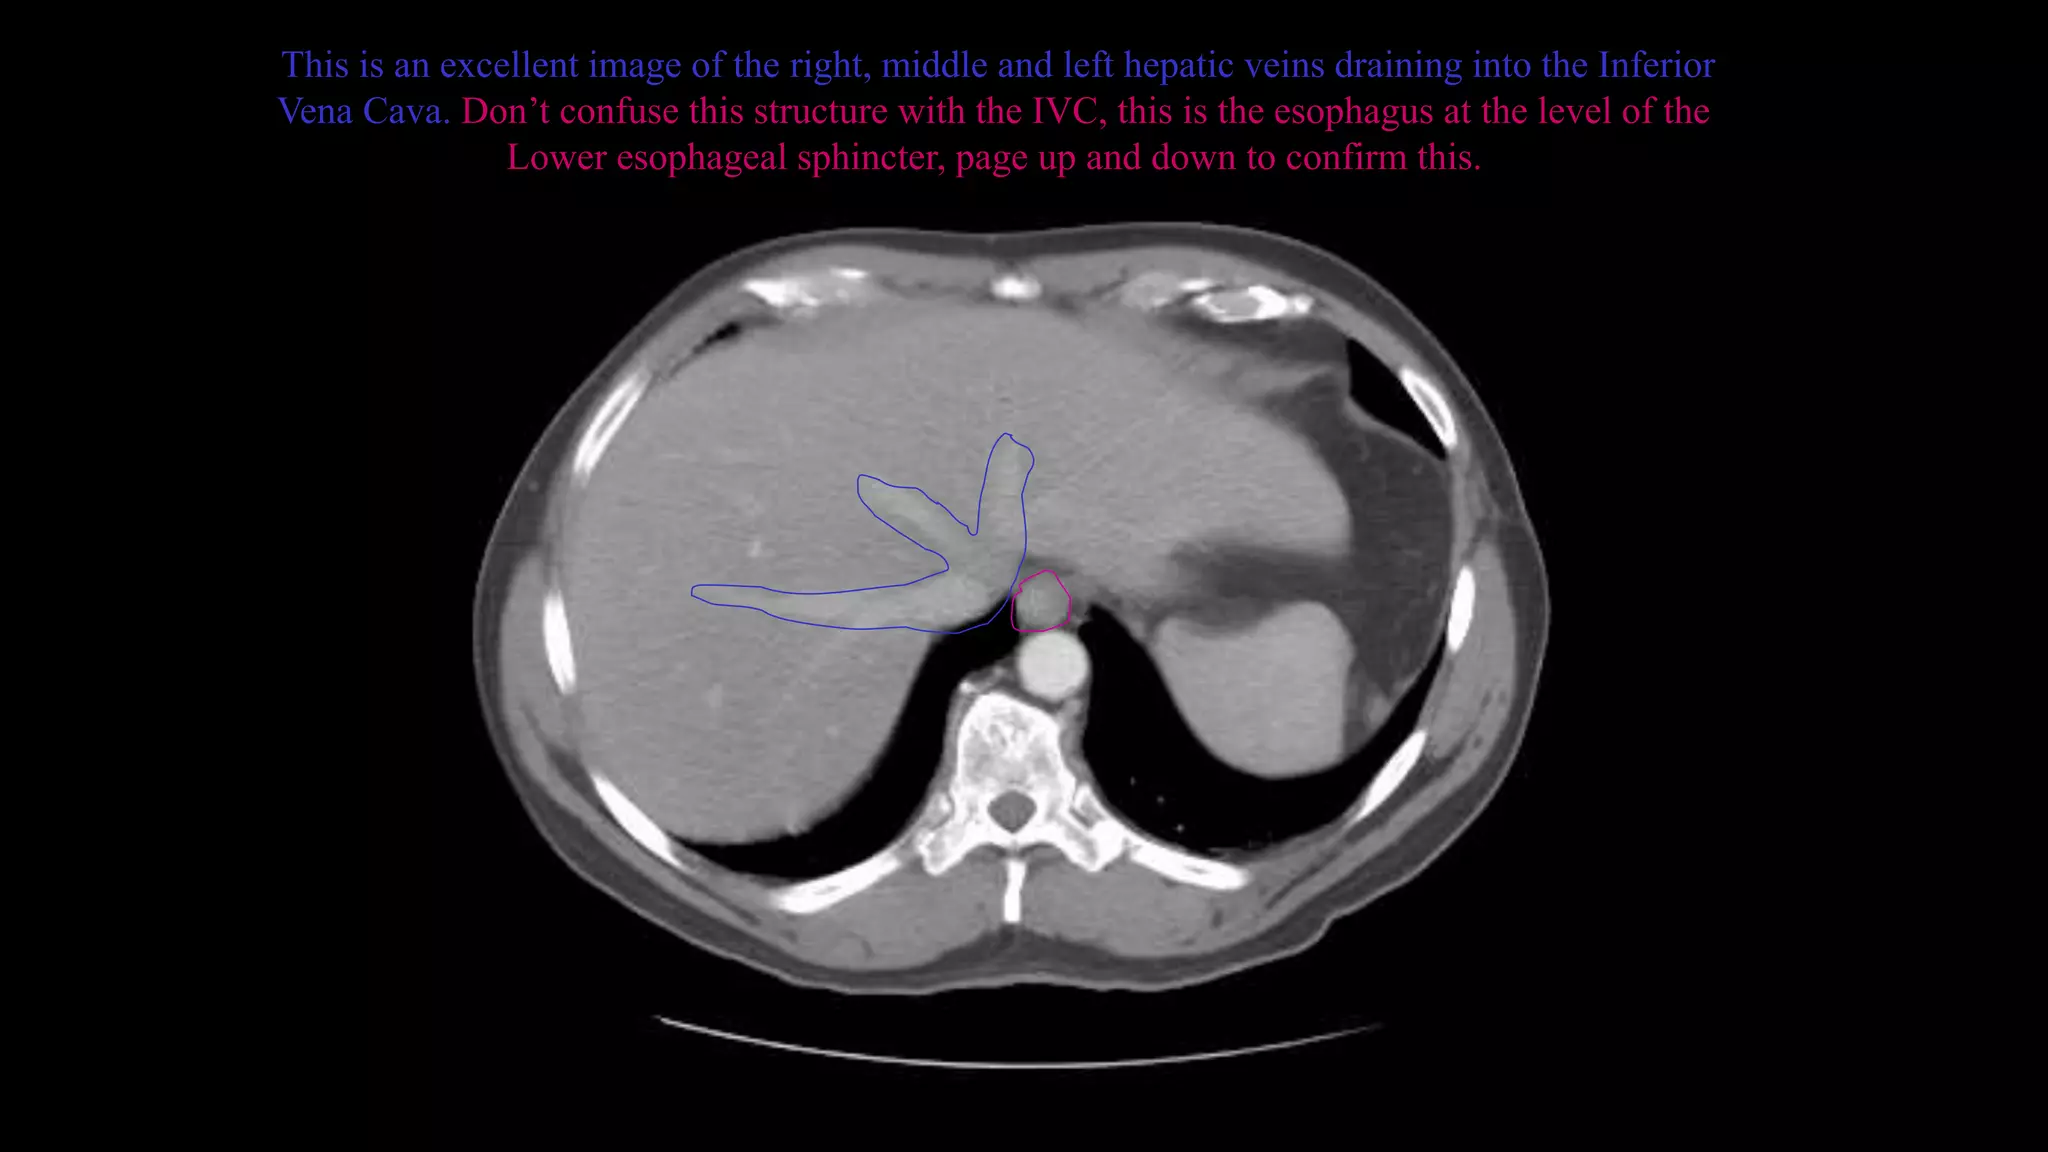

This is an excellent image of the right, middle and left hepatic veins draining into the Inferior

Vena Cava. Don’t confuse this structure with the IVC, this is the esophagus at the level of the

Lower esophageal sphincter, page up and down to confirm this.

This is anexcellent image of the right, middle and left hepatic veins draining into the Inferior Vena Cava. Don’t confuse this structure with the IVC, this is the esophagus at the level of the Lower esophageal sphincter, page up and down to confirm this.